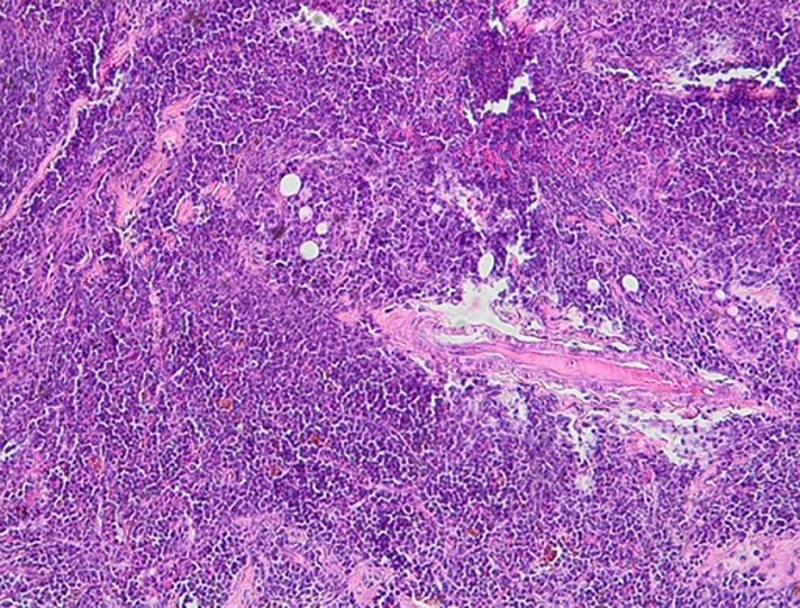

This case presents an 8-year-old girl diagnosed with B-cell acute lymphoblastic leukemia (B-ALL), who relapsed after 3 years of treatment and 1 year of complete remission, with an unusual extramedullary relapse in the ovary. Ovarian relapse of B-ALL is extremely rare in children, making this case noteworthy in scientific literature. The patient had an initial diagnosis of B-ALL with a deletion of chromosome 12, a genetic alteration previously associated with the ETV6-RUNX1 fusion gene, which is typically linked to a favorable prognosis but also carries a 20% risk of late relapse. The relapse was initially asymptomatic and went undetected until clinical symptoms of pelvic pain appeared. Imaging with pelvic ultrasound confirmed the ovarian involvement. The relapse was treated with standard chemotherapy protocols for B-ALL, resulting in a partial response. This case underscores the importance of considering extramedullary relapse in the differential diagnosis for pediatric ALL patients who present with atypical symptoms after remission. It also suggests that routine pelvic ultrasound could be a useful tool for early detection of ovarian and other extramedullary relapses, which are often associated with bone marrow relapse. The main take-away from this case is the necessity for vigilant follow-up, including targeted imaging, in ALL patient's post-remission to ensure early identification of extramedullary relapses, which can otherwise be easily overlooked. The presence of chromosome 12 deletion and its association with late relapse highlights the need for ongoing surveillance even in patients with initial favorable genetic abnormalities.